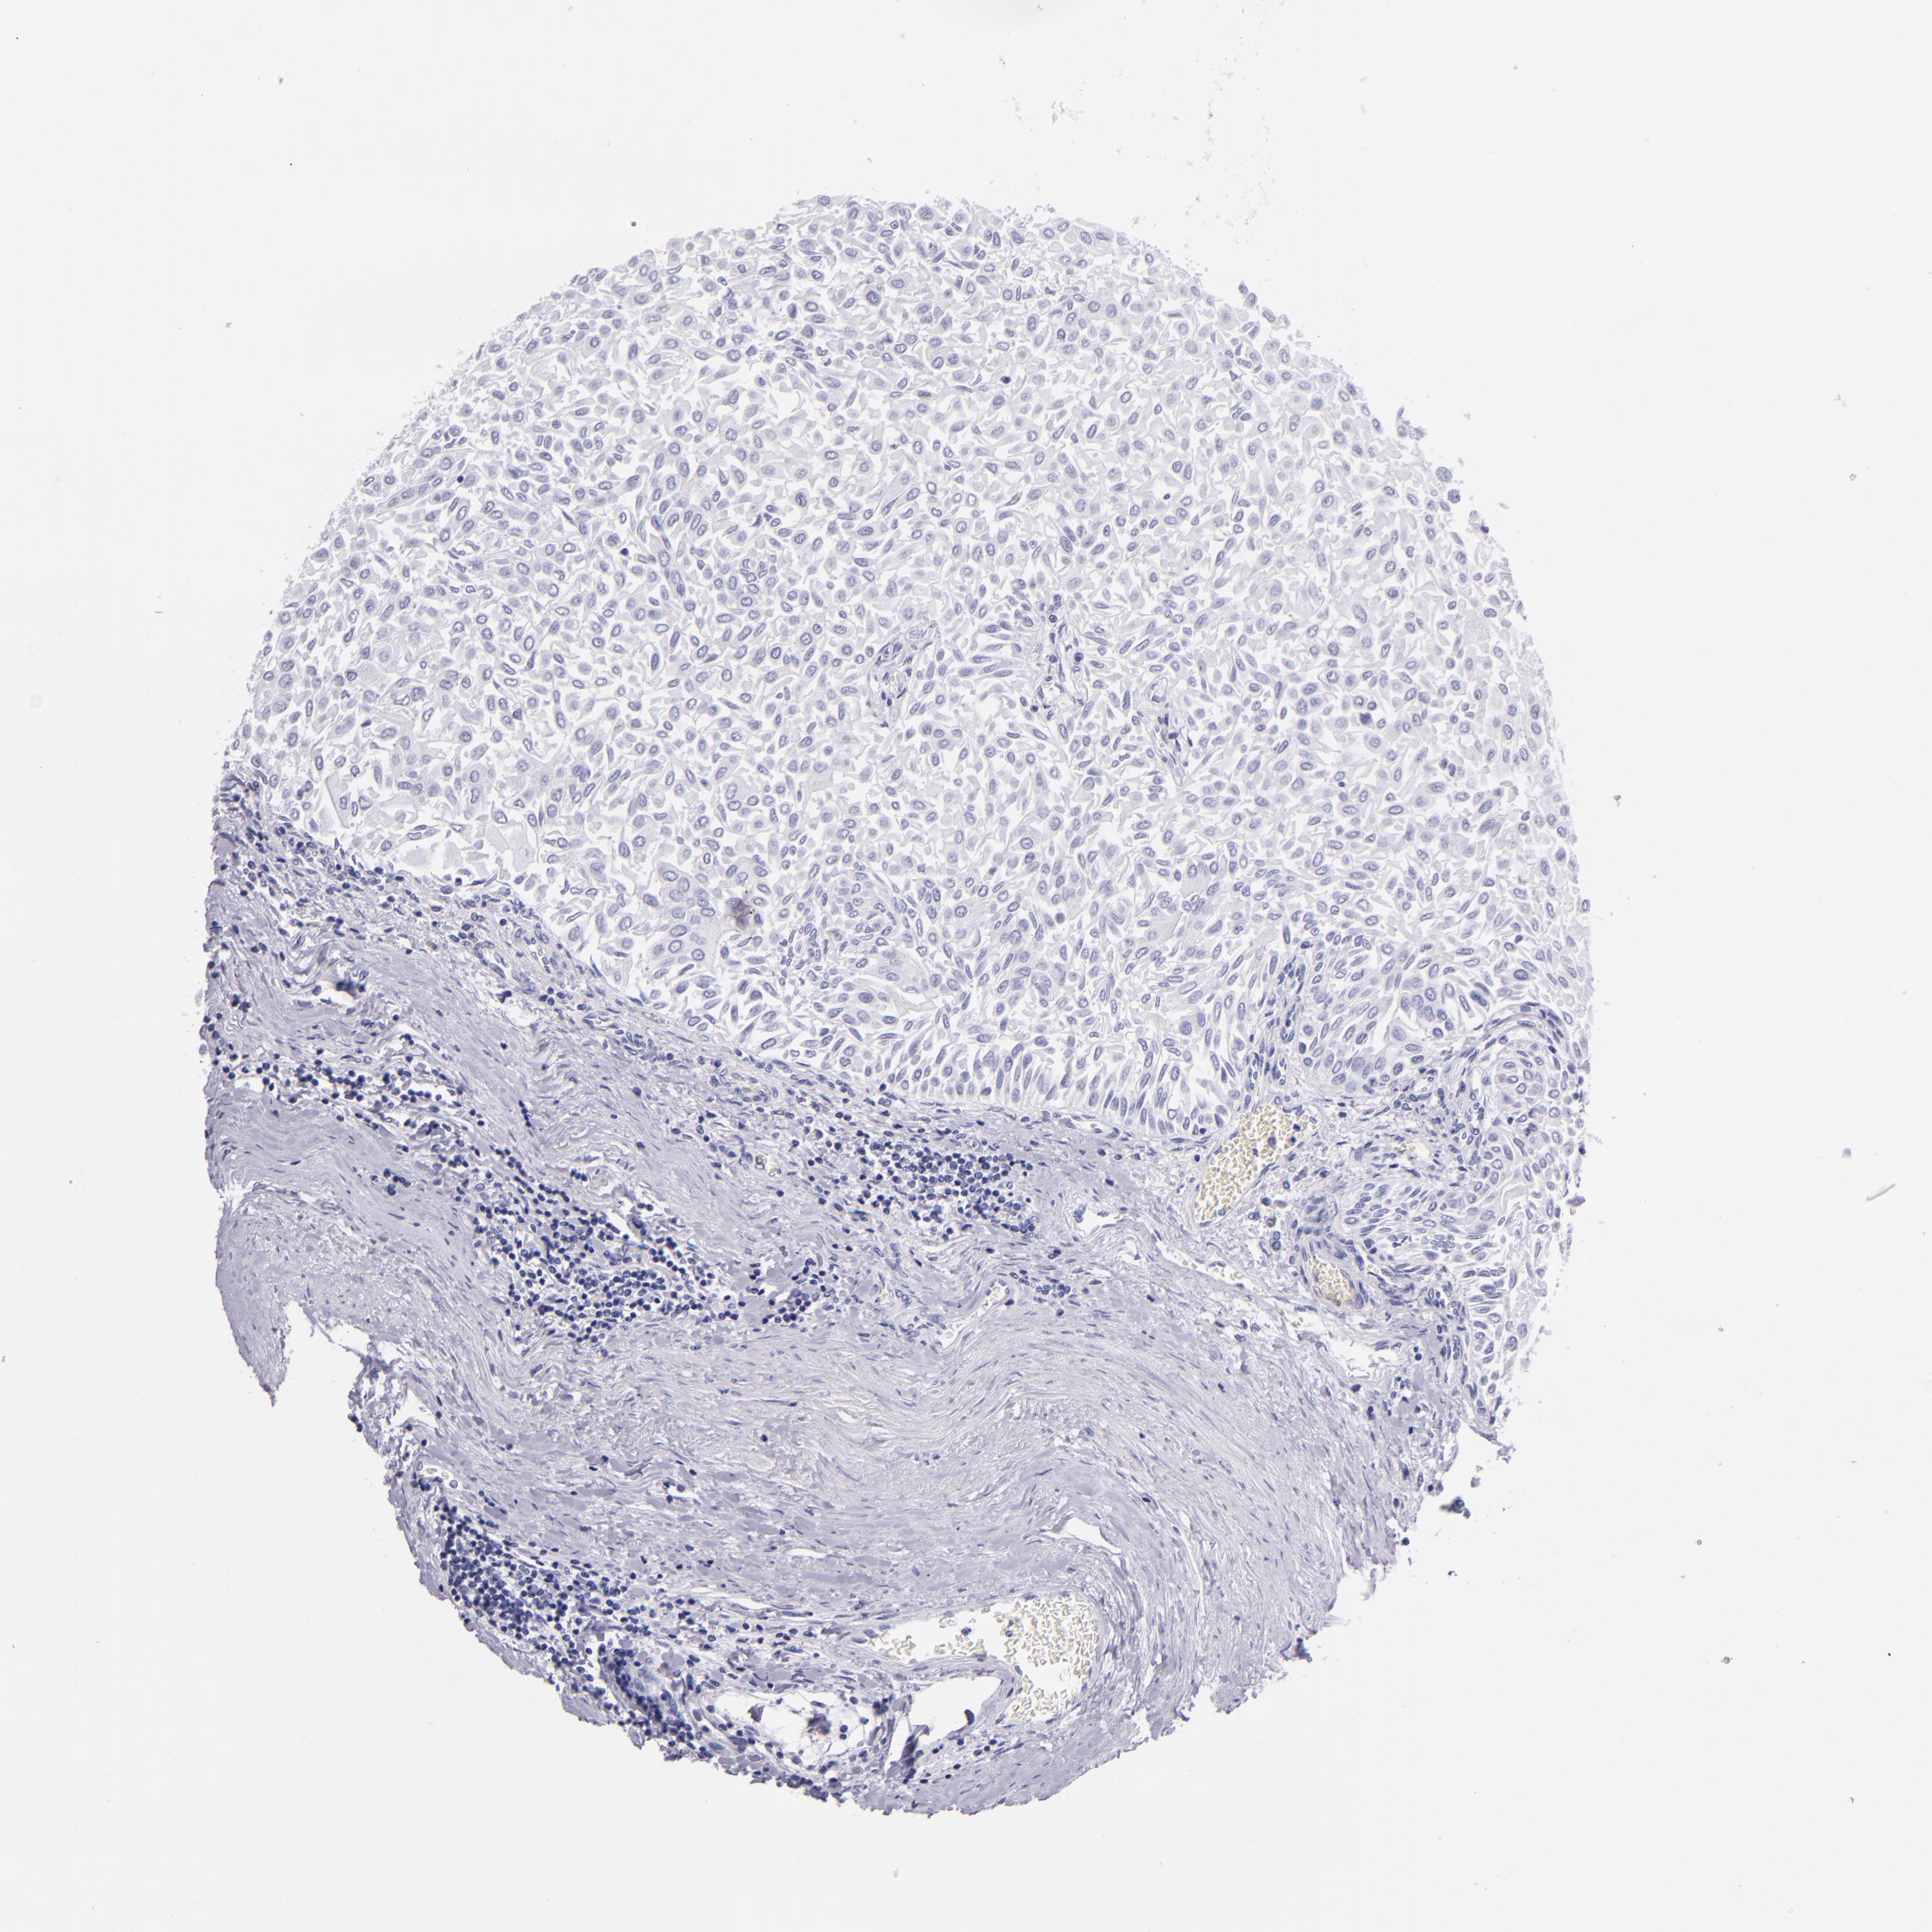

UROTHELIAL CANCER - Protein expressioni

A mouse-over function shows sample information and annotation data. Click on an image to view it in a full screen mode. Samples can be filtered based on level of antibody staining by selecting one or several of the following categories: high, medium, low and not detected. The assay and annotation is described here.

Note that samples used for immunohistochemistry by the Human Protein Atlas do not correspond to samples in the TCGA dataset.

Antibody stainingi

Antibody staining in the annotated cell types in the current human tissue is reported as not detected, low, medium, or high, based on conventional immunohistochemistry profiling in selected tissues. This score is based on the combination of the staining intensity and fraction of stained cells.

Each image is clickable and will lead to virtual microscopy that enables deeper exploration of all samples and also displays staining intensity scores, fraction scores and subcellular localization as well as patient and tissue information for each sample.